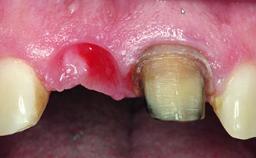

A healthy 37-year-old female patient was referred for a consultation on the replacement of missing tooth 21 with an implant-supported restoration. She stated that several years previously the tooth had been traumatically avulsed following a motor vehicle accident. The tooth was replaced with a three-unit fixed partial denture (FPD) immediately afterwards. Over time, she became disillusioned with the FPD and looked for a different option, including orthodontic therapy. She presented still in her orthodontic appliances, with the pontic sectioned free from the FPD but attached to the archwire. Her orthodontist felt that orthodontic treatment had been successfully completed, but nevertheless referred her before removing the appliances in case adjustments were necessary.